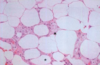

Traumatic fat necrosis

Fat necrosis with lipid-laden macrophages and PMNs